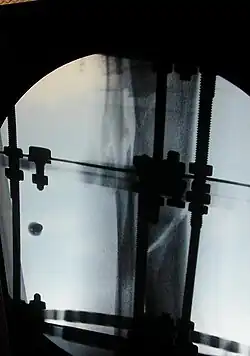

The photographs and radiographs illustrate the application and emplacement of an external fixator, an Ilizarov apparatus, to repair the open fracture of the lower left leg of a man. The photographs were taken four weeks after the patient fractured the shinbone (tibia) and the calfbone (fibula) of his left leg, and two weeks after the surgical emplacement of the Ilizarov apparatus to immobilise the leg and isolate the wound and fracture site to facilitate healing.

X-ray of the fracture site and the emplaced apparatus, two months post-fracture; perspective 1-4.

X-ray of the fracture site and the emplaced apparatus, two months post-fracture; perspective 2-4.

X-ray of the callus forming at the fracture site, three months post-fracture; perspective 3-4.

X-ray of the callus forming around the fracture site, three months post-fracture; perspective 4-4.

X-ray perspectives of the callus-formation progress and healing of the fractured tibia and fibula bones, four months post-fracture.